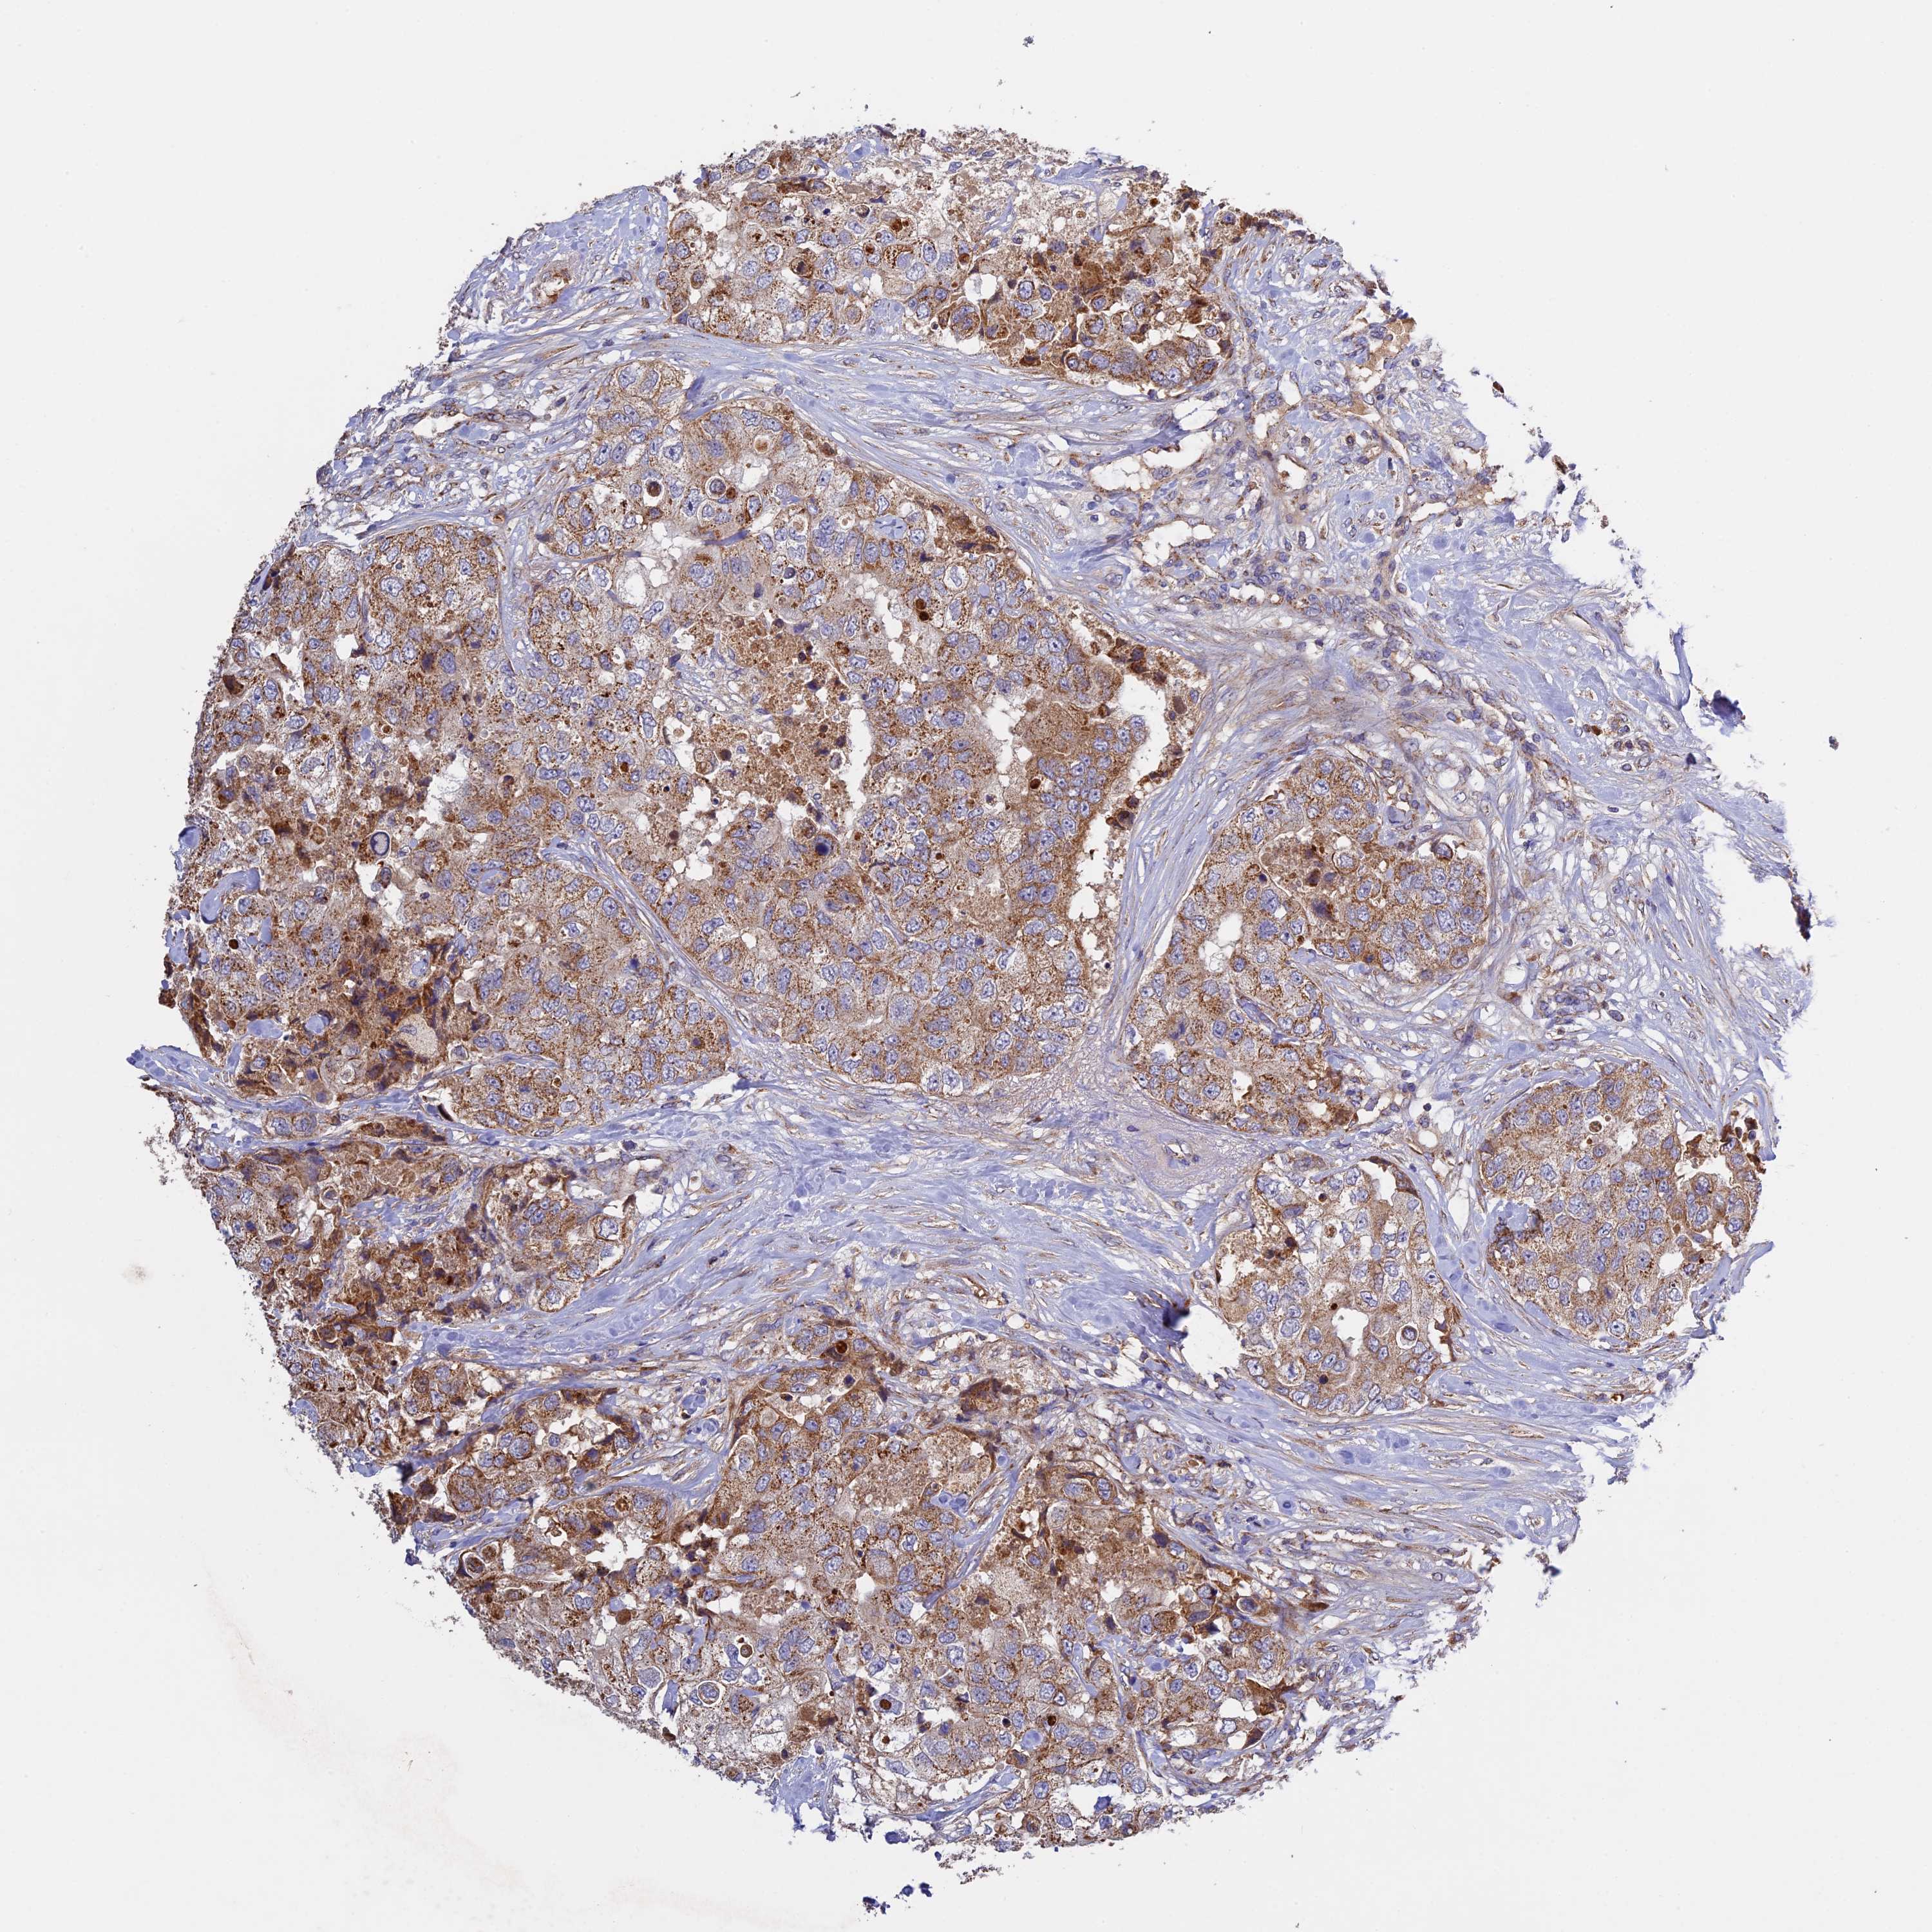

CANCER BREAST CANCER Show tissue menu

BRCA TCGA BRCA VALIDATION PROTEIN EXPRESSION